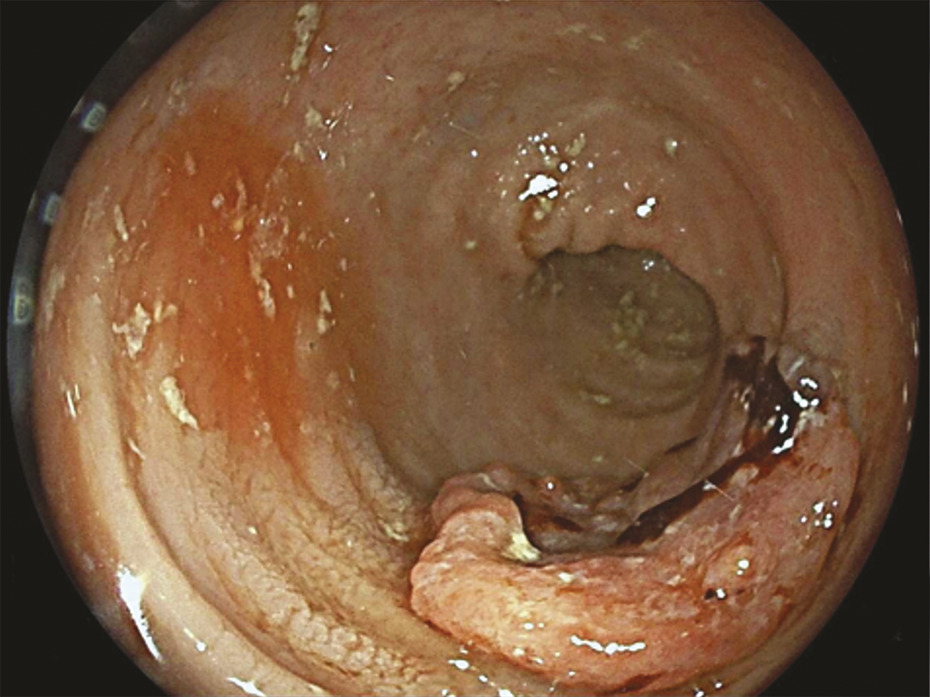

La coloscopie, sous anesthésie générale, est l’examen de première intention dans la plupart des cas de rectorragies. Si elle met en évidence une tumeur rectale, elle peut être complétée immédiatement ou dans un second temps par une rectoscopie rigide, permettant d’évaluer plus précisément la distance entre le pôle inférieur de la tumeur et la marge anale (mesure la plus reproductible) et/ou le pôle supérieur du sphincter. L’examen endoscopique permet également de décrire la lésion rectale (taille, aspect macroscopique, circonférence d’implantation) et de recueillir de multiples biopsies, indispensables au diagnostic (fig. 1 et 2 ).